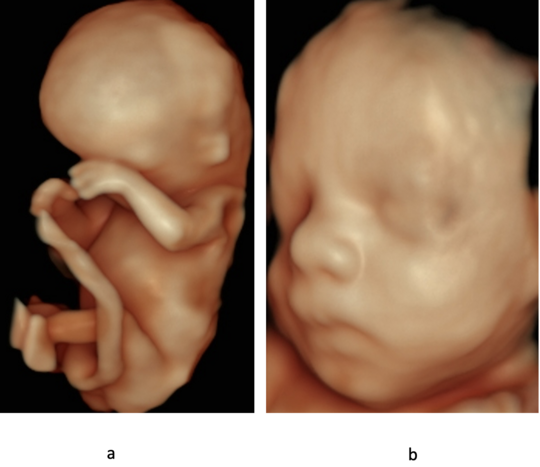

Kindliches Gesicht im Profil

Zahlreiche kindliche Erkrankungen lassen sich mittels einer weiterführenden Feindiagnostik mit hochauflösenden Ultraschallgeräten frühzeitig erkennen. Idealerweise wird diese Untersuchung zwischen der 20. und der 22. Schwangerschaftswoche durchgeführt. Zu diesem Zeitpunkt ist die Entwicklung aller Organe bereits weitgehend abgeschlossen. In unserer Pränataldiagnostik und Schwangerenambulanz wird eine solche Untersuchung von speziell geschultem und erfahrenem Personal durchgeführt.

Im Rahmen der Diagnostik untersuchen wir die kindlichen Organe wie das Herz und die Nieren, aber auch andere Strukturen wie etwa das Gehirn oder Gesicht zum Ausschluss einer Lippen-Kiefer-Gaumenspalte. Auch die Wirbelsäule mit der Fragestellung nach einem offenen Rücken oder die Knochen werden beurteilt.

3D-/4D-Ultraschall

Die 3D-Sonographie erlaubt uns in der Pränataldiagnostik und Schwangerenambulanz die dreidimensionale Darstellung von Strukturen. Bestimmte Auffälligkeiten wie eine Lippen-Kiefer-Gaumen-Spalte oder andere Fehlbildungen können den werdenden Eltern besser aufgezeigt werden. Zudem ist eine dreidimensional dargestellte intakte Struktur im Zweifelsfall auch beruhigend.

Zudem hat die vorgeburtliche 3D-Untersuchung den Vorteil, dass die sehr plastische Darstellung die Mutter-Kind-Bindung verstärkt.

Die Durchführbarkeit hängt im Wesentlichen von den zugrundeliegenden Untersuchungsbedingungen ab. So muss genügend Fruchtwasser vorhanden und die Kindslage günstig sein. Auch Schwangerschaftsalter und die mütterliche Konstitution spielen eine zentrale Rolle.

Allerdings kann der 3D-Ultraschall die konventionelle 2D-Sonografie nicht ersetzen, sondern lediglich ergänzen und sollte daher nicht isoliert eingesetzt werden. 4D-Sonografie bedeutet 3D-Ultraschall am bewegten Bild. Stellen Sie es sich als eine Art 3D-Untersuchung in live vor.